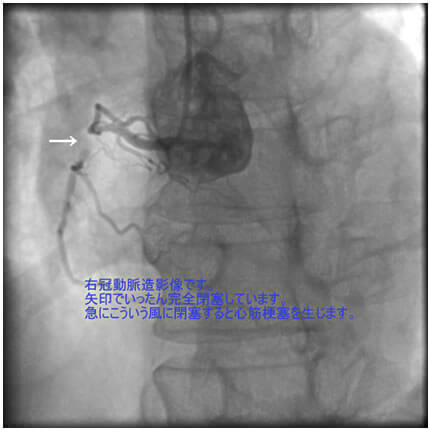

危険因子が特に複合的にあると動脈硬化は加速します。今回は、動脈硬化が加速するとどうなるか、実際の症例でお示しします。なお、お見せします画像は、すべて動画から静止画像にしています。実際には冠動脈造影は動画で見ます。

1番目の患者さんは80歳の男性です。この方の危険因子は高血圧、高脂血症、喫煙です。この方の冠動脈造影と腹部CT画像を示します。図1-1から1-8の画像は全て全てこの患者さんの画像です。

図1-1 右冠動脈造影

よく解らないと思いますが、冠動脈に多数の狭窄があることと冠動脈が「こぶ状変化(医学用語で瘤状変化)」を生じているのが解ると思います。

色々とお目にかけましたが、動脈の硬化により動脈が狭くなったり(狭窄)、太くなる(瘤状変化:りゅうじょうへんか)のがお解りになられたと思います。

これらの患者さんは別に珍しい患者さんではありません。どの患者さんも冠動脈バイパス術に加えて瘤状変化を生じた血管を人工血管に置換する手術を行い、皆さん元気で生活に復帰されています。